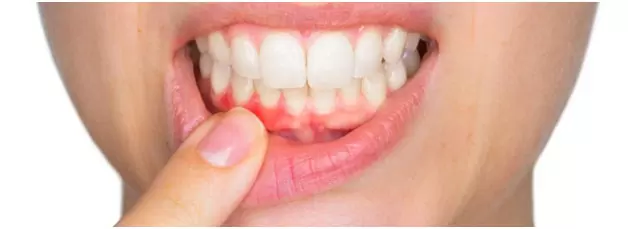

The longer plaque and tartar are on teeth, the more harmful they become. The bacteria cause inflammation of the gums that is called “gingivitis.” In gingivitis, the gums become red, swollen and can bleed easily. Gingivitis is a mild form of gum disease that can usually be reversed with daily brushing and flossing, and regular cleaning by a dentist or dental hygienist.